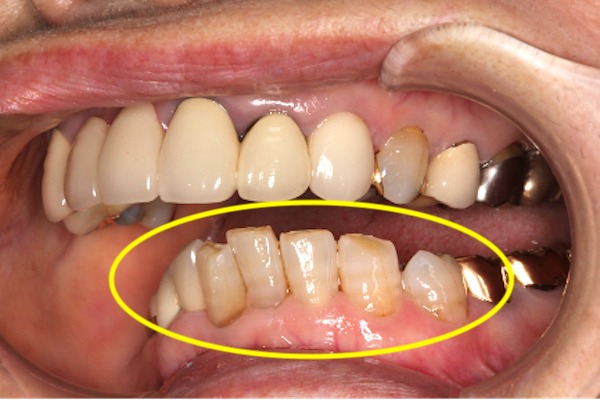

今回の患者様は、下の前歯がでこぼこしながら内側に入り、奥歯に比べて飛び出しています。本来、下の前歯は上の前歯の裏側に当たっているのですが、患者様の場合、下の前歯が上顎に突き刺さるような状態になっていました。

また、上の前歯は何度も治療を繰り返していました。さらに下の前歯の先端は削れていました。下の写真でお分かりでしょうか?

「エナメル質」という、歯の表面の白くて硬い外殻部分が失われ、「象牙質」という、歯の表面から2層目にあたる、少し黄色い部分が露出しています。

下の前歯が異常に削れてしまうというのは、噛み合わせがおかしいことの大事なサインです。